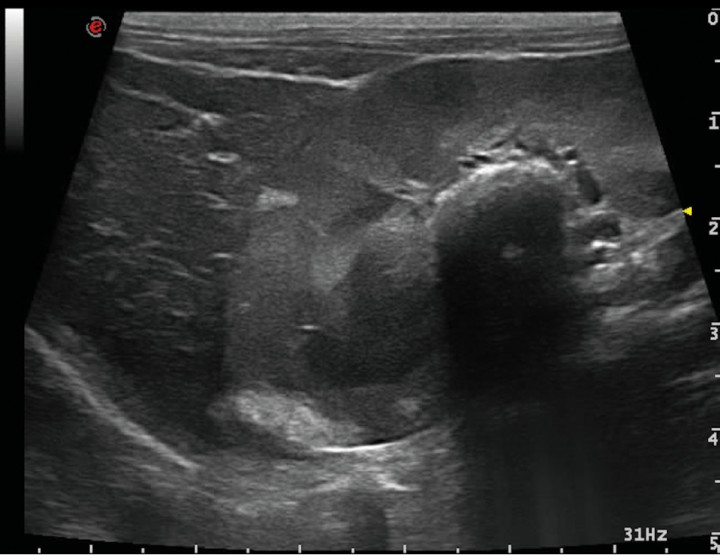

La ecografía hepática mostro un hígado de pequeño tamaño, con presencia de focos hiperecoicos y con sombra acústica (Fig. 2). Los conductos biliares mostraban distensión severa y aspecto tortuoso, manteniendo su comunicación con la vesícula biliar, sin evidencia de obstrucción en algún punto concreto de su recorrido (Fig. 3). La papila duodenal se visualizaba normal. La vena porta presentaba pequeño tamaño, flujo hepatópeto y velocidad aparentemente reducida (Fig. 4). Se evidenció la presencia de múltiples vasos de aspecto tortuoso adyacentes al riñón izquierdo (Fig. 5). Ambos riñones presentan múltiples infartos renales y focos mineralizados en la corteza, sedimento con sombra acústica en pelvis renal izquierda y presencia de cálculos en riñón derecho (Fig. 6). Pequeña cantidad de líquido libre anecoico (Fig. 7).

<p>Corte longitudinal a nivel del riñón derecho - hígado. Área hiperecoica con marcada sombra acústica en región de pelvis renal (urolitiasis) y múltiples áreas hiperecoicas de forma acuñada, sin sombra acústica en región cortical (infartos renales).</p>

Figura 6

Corte longitudinal a nivel del riñón derecho - hígado. Área hiperecoica con marcada sombra acústica en región de pelvis renal (urolitiasis) y múltiples áreas hiperecoicas de forma acuñada, sin sombra acústica en región cortical (infartos renales).

¿A nivel clínico, qué nos sugiere la presencia de un hígado de pequeño tamaño, renomegalia bilateral y urolitiasis?

Estos hallazgos suelen aparecer de forma secundaria a la reducción del flujo venoso portal al hígado. La microhepatía puede observarse en caso de hipoplasia primaria de la vena porta, hepatitis crónica o cirrosis, y la renomegalia bilateral puede verse en caso de trastorno hipertensivo portal congénito, pero la combinación de estos tres hallazgos se ha visto que tiene un valor predictivo positivo del 100% de presencia de trastorno vascular hepático.[ d’Anjou MA, Penninck DG, Cornejo L, Pibarot P (2004) Ultrasonographic diagnosis of portosystemic shunting in dogs and cat. Vet Radiol Ultrasound 45:424-437. [PubMed] ]